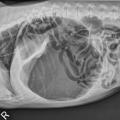

Toks pacientas laikomas kritiniu, todėl nedelsiant atliekamas būklės stabilizavimas, diagnostika – dažniausiai pilvo rentgenograma, ir skubi operacija – iš skrandžio pašalinamos susikaupusios dujos ir kitas turinys, skrandis fiksuojamas prie pilvo sienos, kad tokia patologija daugiau nepasikartotų (atliekama gastropeksija).

Pav. nr. 2 Užsisukusio ir išsiplėtusio skrandžio vaizdas pilvo rentgenogramoje https://vetgirlontherun.com/wp-content/uploads/2014/01/GDVSeimRad.jpg